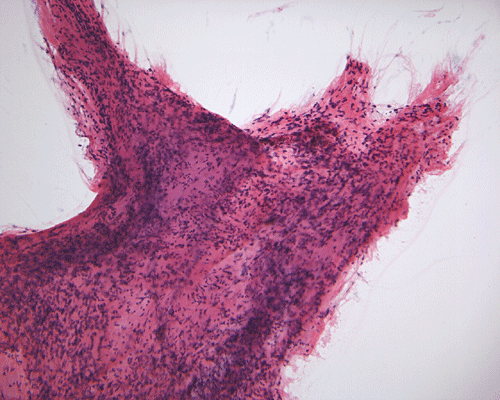

Pathology of the case: A small specimen was obtained by endoscopic biopsy. The specimen cannot be smear out after being squashed and remain as several, large, stellate-shaped cohesive clumps (Panel D). The edges of these clumps are relatively thin and allows better observations. The nuclei do not appear to be pleomorphic. Many elongated cytoplasmic processes can be seen (Panel E) and are suggest a glial nature of these cells. The lesion gives a spongy appearance on low-magnification (Panel F). On medium-magnification, there are some clustering of nuclei (Panel G). On high-magnification, the nuclei appear hyperchromatic and pointy but no substantial pleomorphism, prominent nucleoli, or mitotic figure. Some bluish, mucoid material is identified in some microcysts (Ú in Panel H).